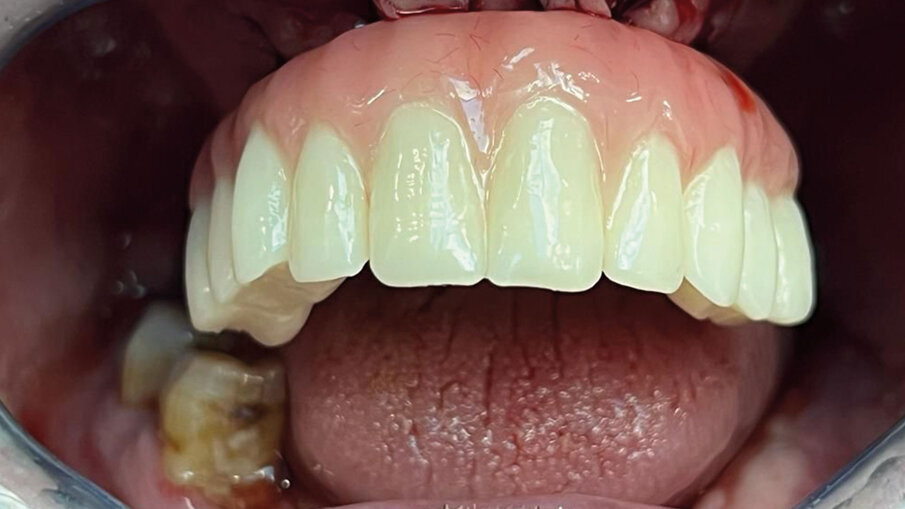

Fig. 9 - Foto vista completa dopo aver inserito i monconi.

Fig. 10 - RX dopo 3 Mesi. Si è proceduto con l’inserimento dei monconi più provvisorio fisso.

Fig. 11 - Fotografia con vista frontale prima dell’inserimento dei monconi.

Fig. 12 - Inserimento provvisori - vista frontale.

Fig. 13 - Senza provvisori - vista laterale.

Fig. 14 - Inserimento provvisori - vista laterale.

Fig. 15 - Inserimento dei denti provvisori subito dopo aver avvitato i monconi sul Device.